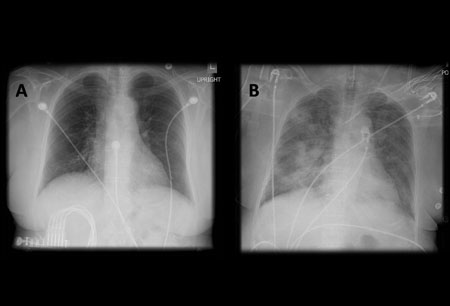

A. Radiografía portátil de tórax en posición erguida antes de la aspiración; B. Radiografía de tórax 1 hora después de la aspiración, en la que se muestran infiltrados alveolares difusos bilaterales, peores en las bases del lado derecho

De la colección personal del Dr. S. Murgu y el Dr. H. Colt, University of California en Irvine Medical Center